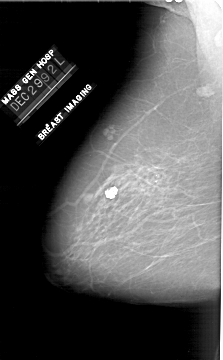

A_1910_1.RIGHT_CC

RIGHT_CC LINES 6196 PIXELS_PER_LINE 3406 BITS_PER_PIXEL 12 RESOLUTION 43.5 OVERLAY